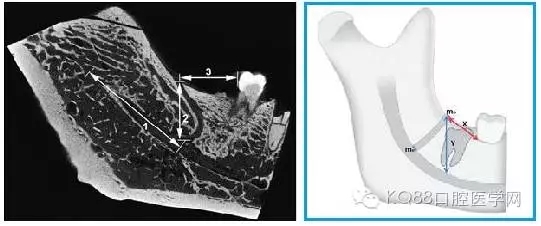

圖四 磨牙后管的線性測量

1.從下頜孔到下頜磨牙后管分支起點的距離;

2.下頜磨牙后管的垂直高度(X)

3.從下頜后孔到第二或第三磨牙遠中的水平距離(Y)。